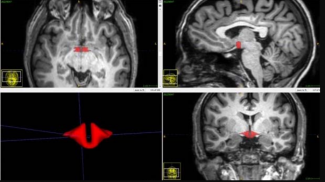

Štúdia: Antikoncepčná tabletka môže umenšovať určité mozgové oblasti u žien